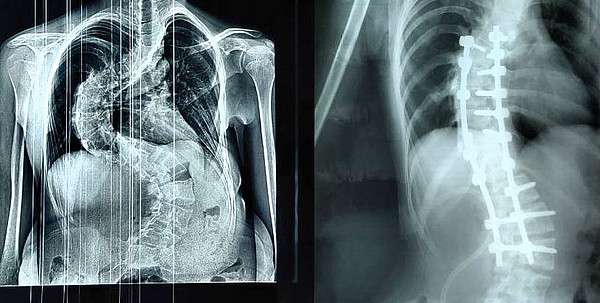

Сколиоз_4 стСколиоз_4 ст_

Сколиоз_4 ст.